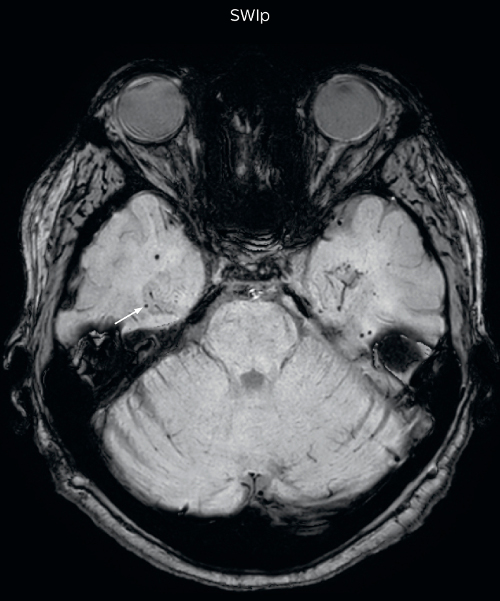

“With SWIp we are basically looking for blood byproducts. It is a sensitive method for visualizing small lesions containing deoxygenated blood. In our comparison, SWIp images are vastly better than gradient echo imaging, there’s no question of that anymore.” “We find the SWIp images very useful in three areas in particular. In patients with a history of hypertension, it offers clear visualization of hemosiderin deposition from hypertensive hemorrhages. We certainly see a greater number of foci of hemosiderin deposition on the SWIp images than on the T2* gradient echo images. In addition, it also helps us visualize amyloid depositions in patients with amyloid angiopathy.” Dr. Nickerson mentions trauma patients are the third large area where SWIp is useful. “We benefit from SWIp in trauma patients, certainly in cases with diffuse axonal injury and shearing injuries. Our study shows that SWIp usually provides us better visualization,” he says. “Apart from these three, SWIp also helps us to beautifully depict the normal venous anatomy in patients with venous outflow issues or vascular congestion. In some cases, we have seen downstream effects of arterial problems. And in patients with vascular malformations we have seen deposition of blood products associated with those.”

“We switched over entirely. SWIp is now included in all our routine brain exams. We developed two different SWIp sequences: a high spatial resolution (0.5 x 0.5 mm) version that takes 5.5 minutes and our fast SWIp that takes just three minutes. Only in patients that are moving tremendously we occasionally still acquire a gradient echo sequence.” “For us, SWIp use has resulted in more diagnostic confidence when small lesions, such as small shear injuries, vascular malformations, or minute amounts of calcification, need to be detected,” says Dr. Nickerson. “Our physicians greatly value the SWIp images. When we get patients transferred from other facilities with SWIp missing from their exam, we have several neurologists and neurosurgeons who order a new MRI exam because they want to see the SWIp images.”

Gradient echo imaging and SWIp are compared in a patient with radiation-induced foci of hemosiderin deposition. A greater number of small foci is seen on the SWIp image. Ingenia 3.0T